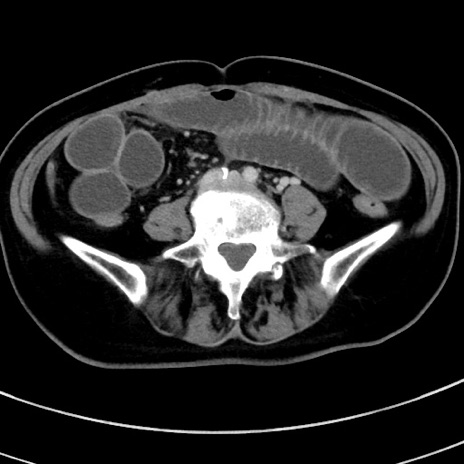

冠状断像

【症例】 60歳代女性

【主訴】むかつき、みぞおちの痛み

【現病歴】3日前よりむかつきがあり、食事がとれない。

【既往歴】糖尿病

【身体所見】発熱なし、心窩部圧痛軽度あるも、腹膜刺激症状なし。

【データ】WBC 7400、CRP 1.92